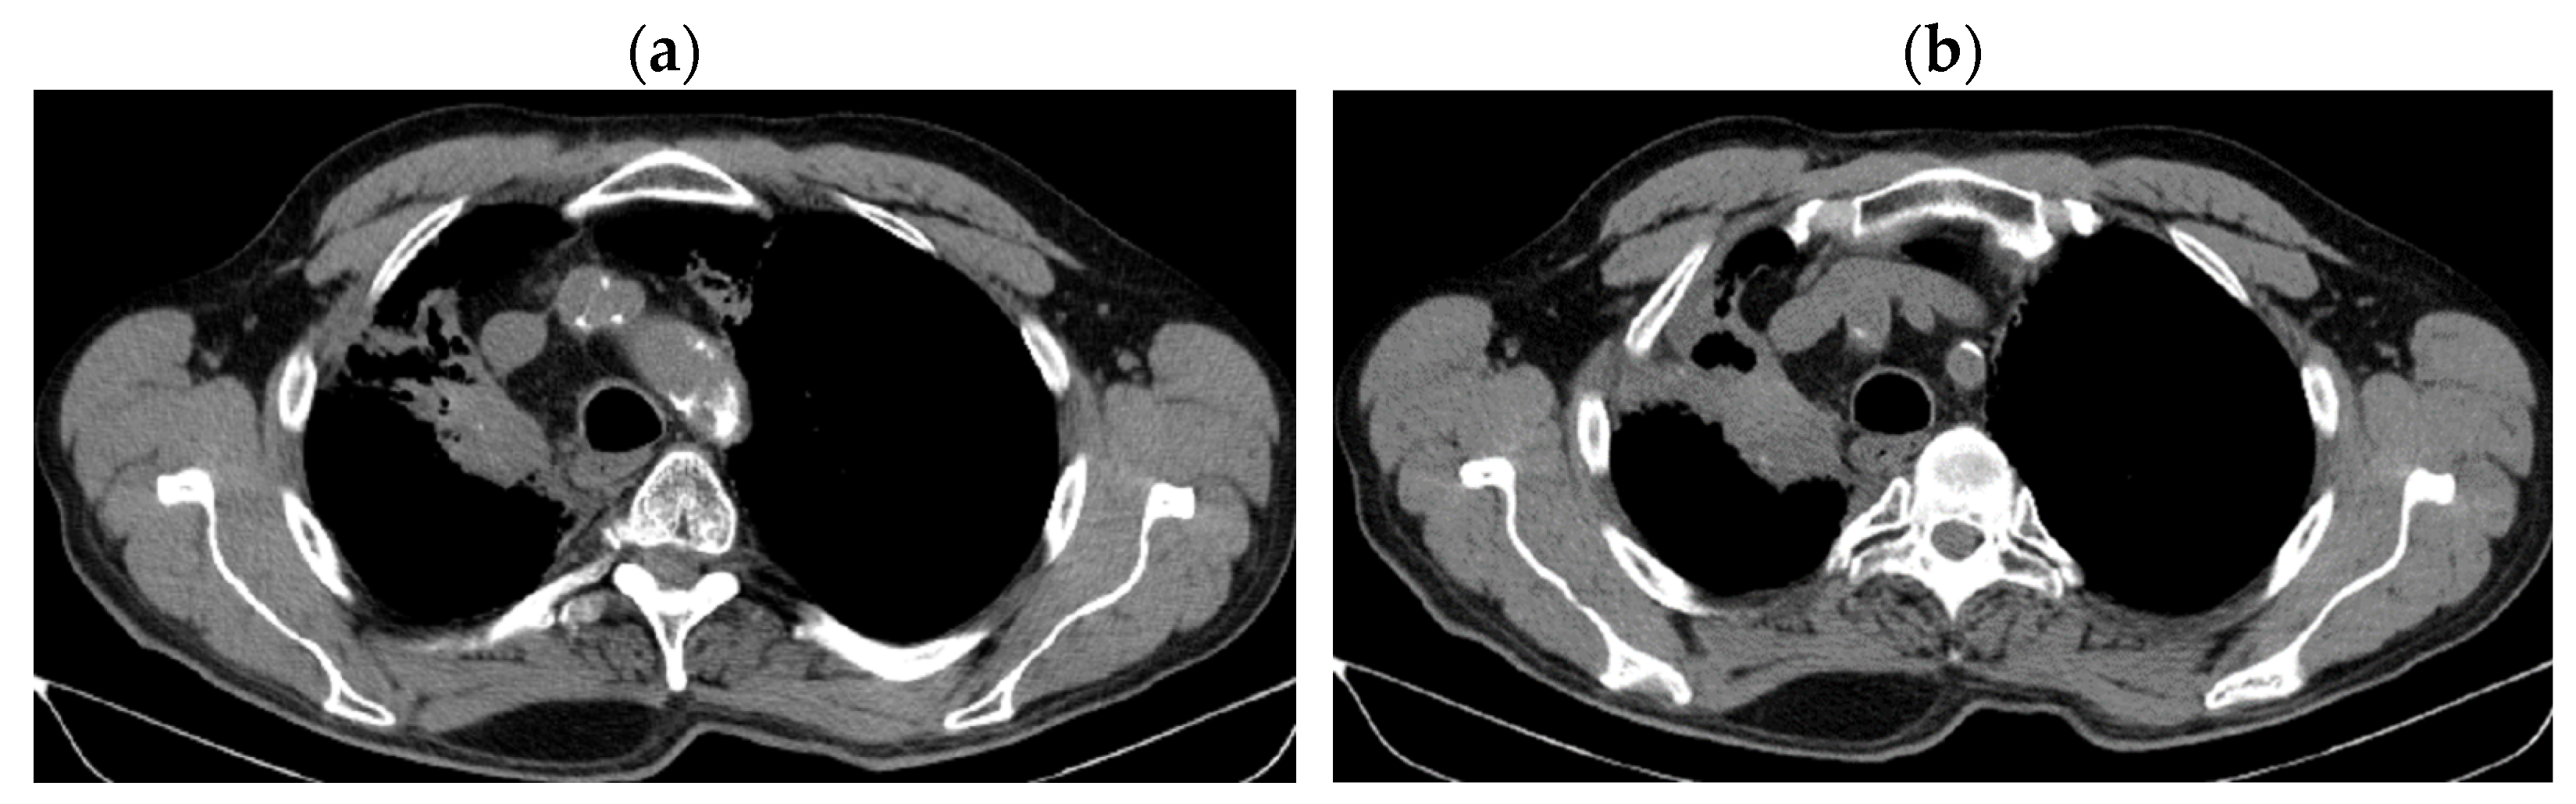

3. Case Results

| DOWNSTAGING from metastatic to locoregional stage | From cT3N3M1b(OSS) stage IVA | In cT2bN3M0, stage IIIB (without M1OSS) |